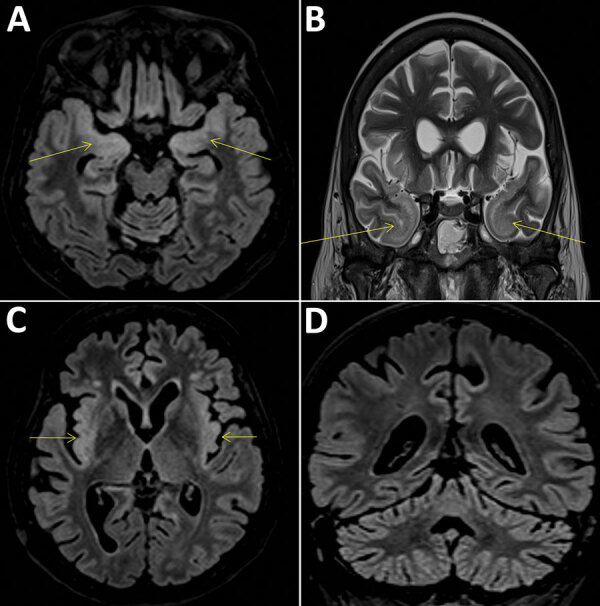

Description:We report the discovery of a new orthobunyavirus, Cristoli virus, by means of shotgun metagenomics. The virus was identified in an immunodepressed patient with fatal encephalitis. Full-length genome sequencing revealed high-level expression of a virulence factor, possibly explaining the severity of the infection. The patient's recent history suggests circulation in France.